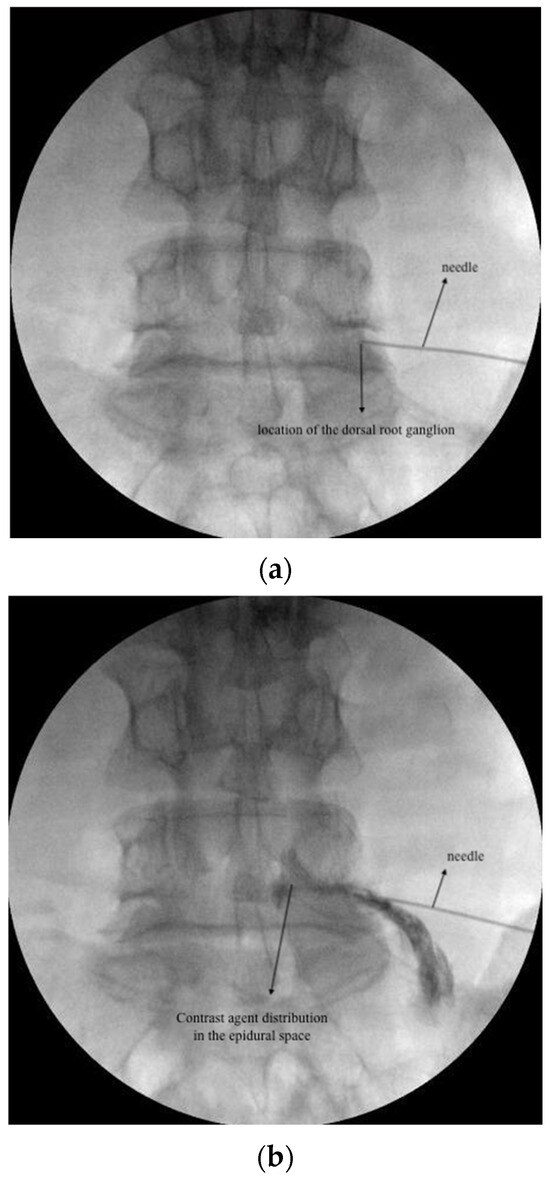

2.3.2. CESI